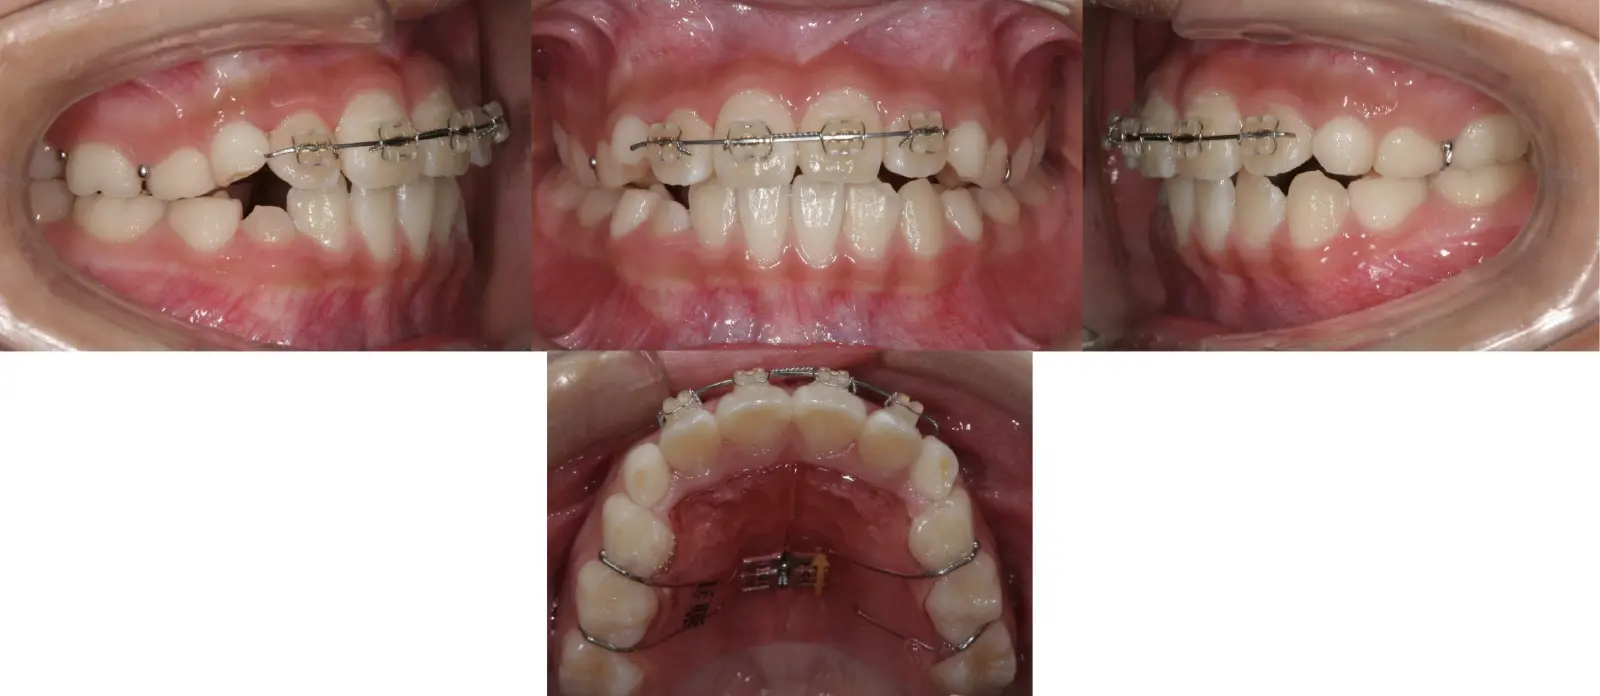

アングルⅡ級 叢生を伴う軽度上顎前突症

第一段階の治療のみで、

永久歯は問題なく萌出し、安定している

- 主訴

前歯のガタガタ

- 年齢

9歳

- 治療期間

10ヶ月

- 治療回数

10回

- 治療に用いた主な装置

拡大床、2by4

- 治療費

400,000円(税別)トータル料金

- 抜歯部位

非抜歯